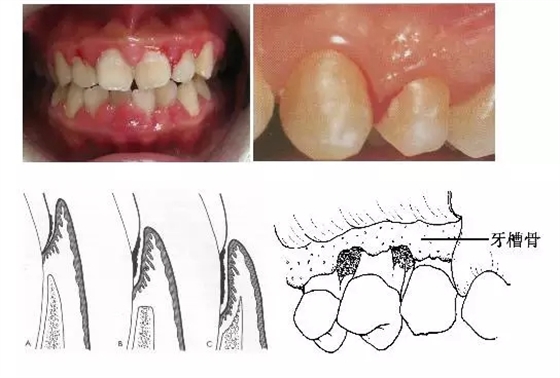

1、牙齦改變:正常牙齦粉紅色、菲薄而緊貼牙面,附著齦有點彩。患牙齦炎時游離齦和齦乳頭呈鮮紅或暗紅色,齦緣變厚,齦乳頭圓鈍,不再緊貼牙面;由于結締組織內(nèi)炎性浸潤及膠原纖維消失,使原來致密堅韌的牙齦變得松軟脆弱,缺乏彈性;同時由于牙齦腫脹或增生,齦溝深度增加,但上皮附著水平仍位于正常的釉牙骨質界,即出現(xiàn)假牙周袋。

3、牙周袋形成:牙周袋是病理性加深的齦溝,是牙周炎最重要的病理改變之一。按照袋底的位置,可將牙周袋分為骨上袋和骨下袋;按牙周袋累及牙面的情況可將其分為單面袋、復合袋、復雜袋。

4、牙槽骨吸收:牙槽骨吸收是牙周炎的另一個主要病理變化,由于牙槽骨的吸收,使牙齒的支持組織喪失,牙齒逐漸松動,最終脫落或拔除。牙槽骨的吸收可分為水平吸收、垂直吸收、凹坑狀吸收等幾種類型。

5、牙齒松動和移位:由于牙周炎使牙槽骨吸收,牙周支持組織減少是牙齒松動的最主要原因;另外在咬頜創(chuàng)傷合并有牙周炎時,也可造成牙齒松動。由于患有牙周炎的牙齒缺乏牙周支持組織,所以,在咬頜創(chuàng)傷的不良咬頜力作用下,牙齒可出現(xiàn)病理性移位。